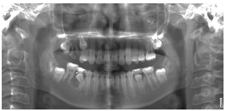

患者,女性,11岁,2018年3月以"右下后牙区囊肿及右上后牙残根2月余"为主诉就诊。患者约2年前治疗口内多颗坏牙,45行根管治疗,16行充填治疗,治疗后未定期复查,16牙冠逐渐脱落,于外院拍片检查发现16残根,右下后牙区囊肿。患者既往体检,无全身病史,父母均健康,无类似病史。检查见:16残根,近远中边缘深达龈下2~3 mm,颊舌边缘位于龈上1.0~1.5 mm,大量腐质。15,17未萌出,46和44之间间隙约2 mm(图1)。曲面断层片显示:16残根,根尖区见低密度影,15阻生,牙根发育Nolla 8期,17牙根发育Nolla 7期,18牙根发育Nolla 5期(图2)。44-46颊侧牙槽骨膨隆,质地硬,无压痛,未及波动感,85远中及牙合面大面积充填体,边缘欠密合,不松动。曲面断层片显示:85牙根大部分吸收,远中根剩余约1mm,根管内见根充影像,45牙轴偏向远中,牙根发育Nolla 8期,44远中至46近中范围可见大面积低密度影,边缘清晰,包绕于45牙颈部。CBCT显示:低密度影近卵圆形,大小约为1.0 cm×1.2 cm×1.4 mm,边界清楚,颊侧骨板薄(图3)。